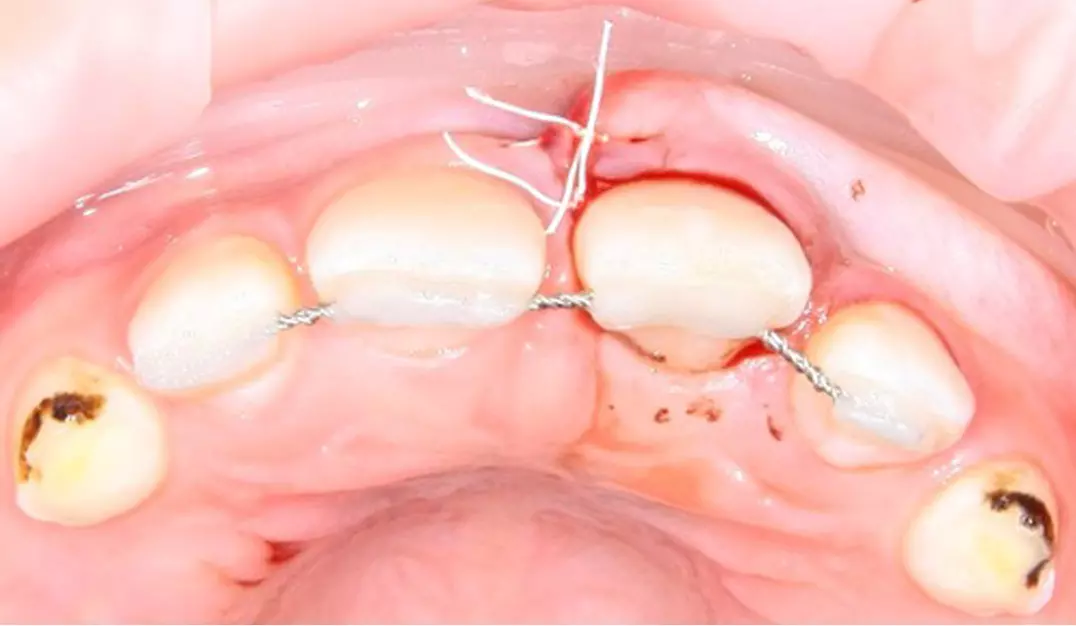

реплантация зуба с последующим шинированием

Пример реплантации зуба с последующим шинированием

После этого врач проводит контрольный рентген-снимок зуба и шинирование. Для реплантации подходит гибкое шинирование (при помощи фрагмента ортодонтического ретейнера или стекловолоконной нити). Через 2-3 недели шину удаляют.